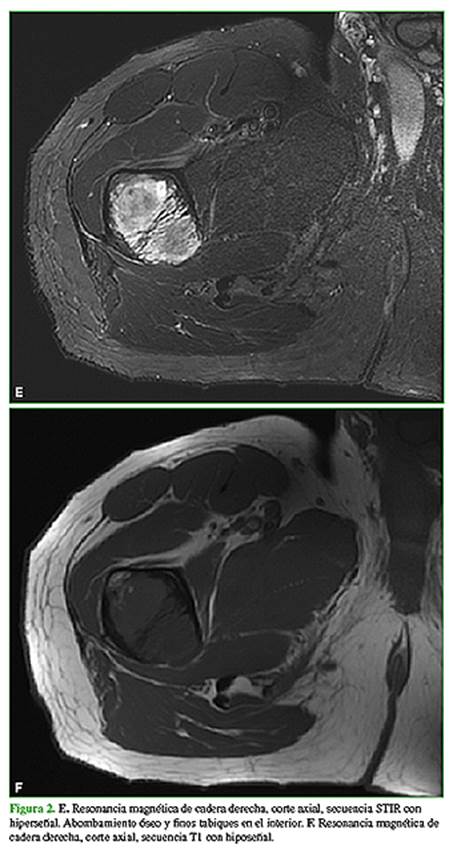

En febrero de 2020, consulta a un traumatólogo de nuestro centro. En el examen físico, la movilidad de la cadera y la rodilla es completa, sin dolor en el miembro inferior derecho. Además, se palpa una tumoración en la zona anteroexterna proximal de la pierna derecha de aproximadamente 8 cm, profunda, elástica, no dolorosa (Figura 1) que, según el paciente, tenía desde los 17 años de edad y su crecimiento era lento. Se solicitan nuevas radiografías y una resonancia magnética de cadera y pierna, y una ecografía de la masa de partes blandas en la pierna (Figura 2).

En las radiografías, se visualiza como lesiones intramedulares diafisarias, radiolúcidas, con apariencia de “vidrio esmerilado” y pérdida del patrón trabecular normal, compromiso endóstico y adelgazamiento de la cortical con áreas respetadas. Los márgenes son definidos. No se observa una reacción perióstica. Las imágenes de la tomografía computarizada confirman la presencia de lesiones homogéneas con apariencia de “vidrio esmerilado”. Puede haber áreas quísticas y calcificaciones. En la resonancia magnética, se observan lesiones con baja señal en las secuencias T1 y alta señal en las secuencias T2. Puede haber un halo hipointenso a su alrededor en las secuencias T1 y T2. Como es una lesión benigna, tiene difusión facilitada con valores de coeficiente de difusión aparente por encima de 1,1 x 10-3 mm2/s.1,2,10

Las radiografías son normales, aunque los mixomas intramusculares se pueden manifestar con calcificaciones no específicas en partes blandas. En la ecografía, los mixomas intramusculares se visualizan como masas ovoideas, poco definidas e hipoecoicas, con posibles áreas quísticas. En la tomografía computarizada, aparecen como lesiones hipointensas con pared que las separa del tejido muscular. En la resonancia magnética, se visualizan como lesiones hiperintensas en las secuencias T2, gradiente de eco o STIR. Las secuencias T1 muestran baja señal.2,6-9